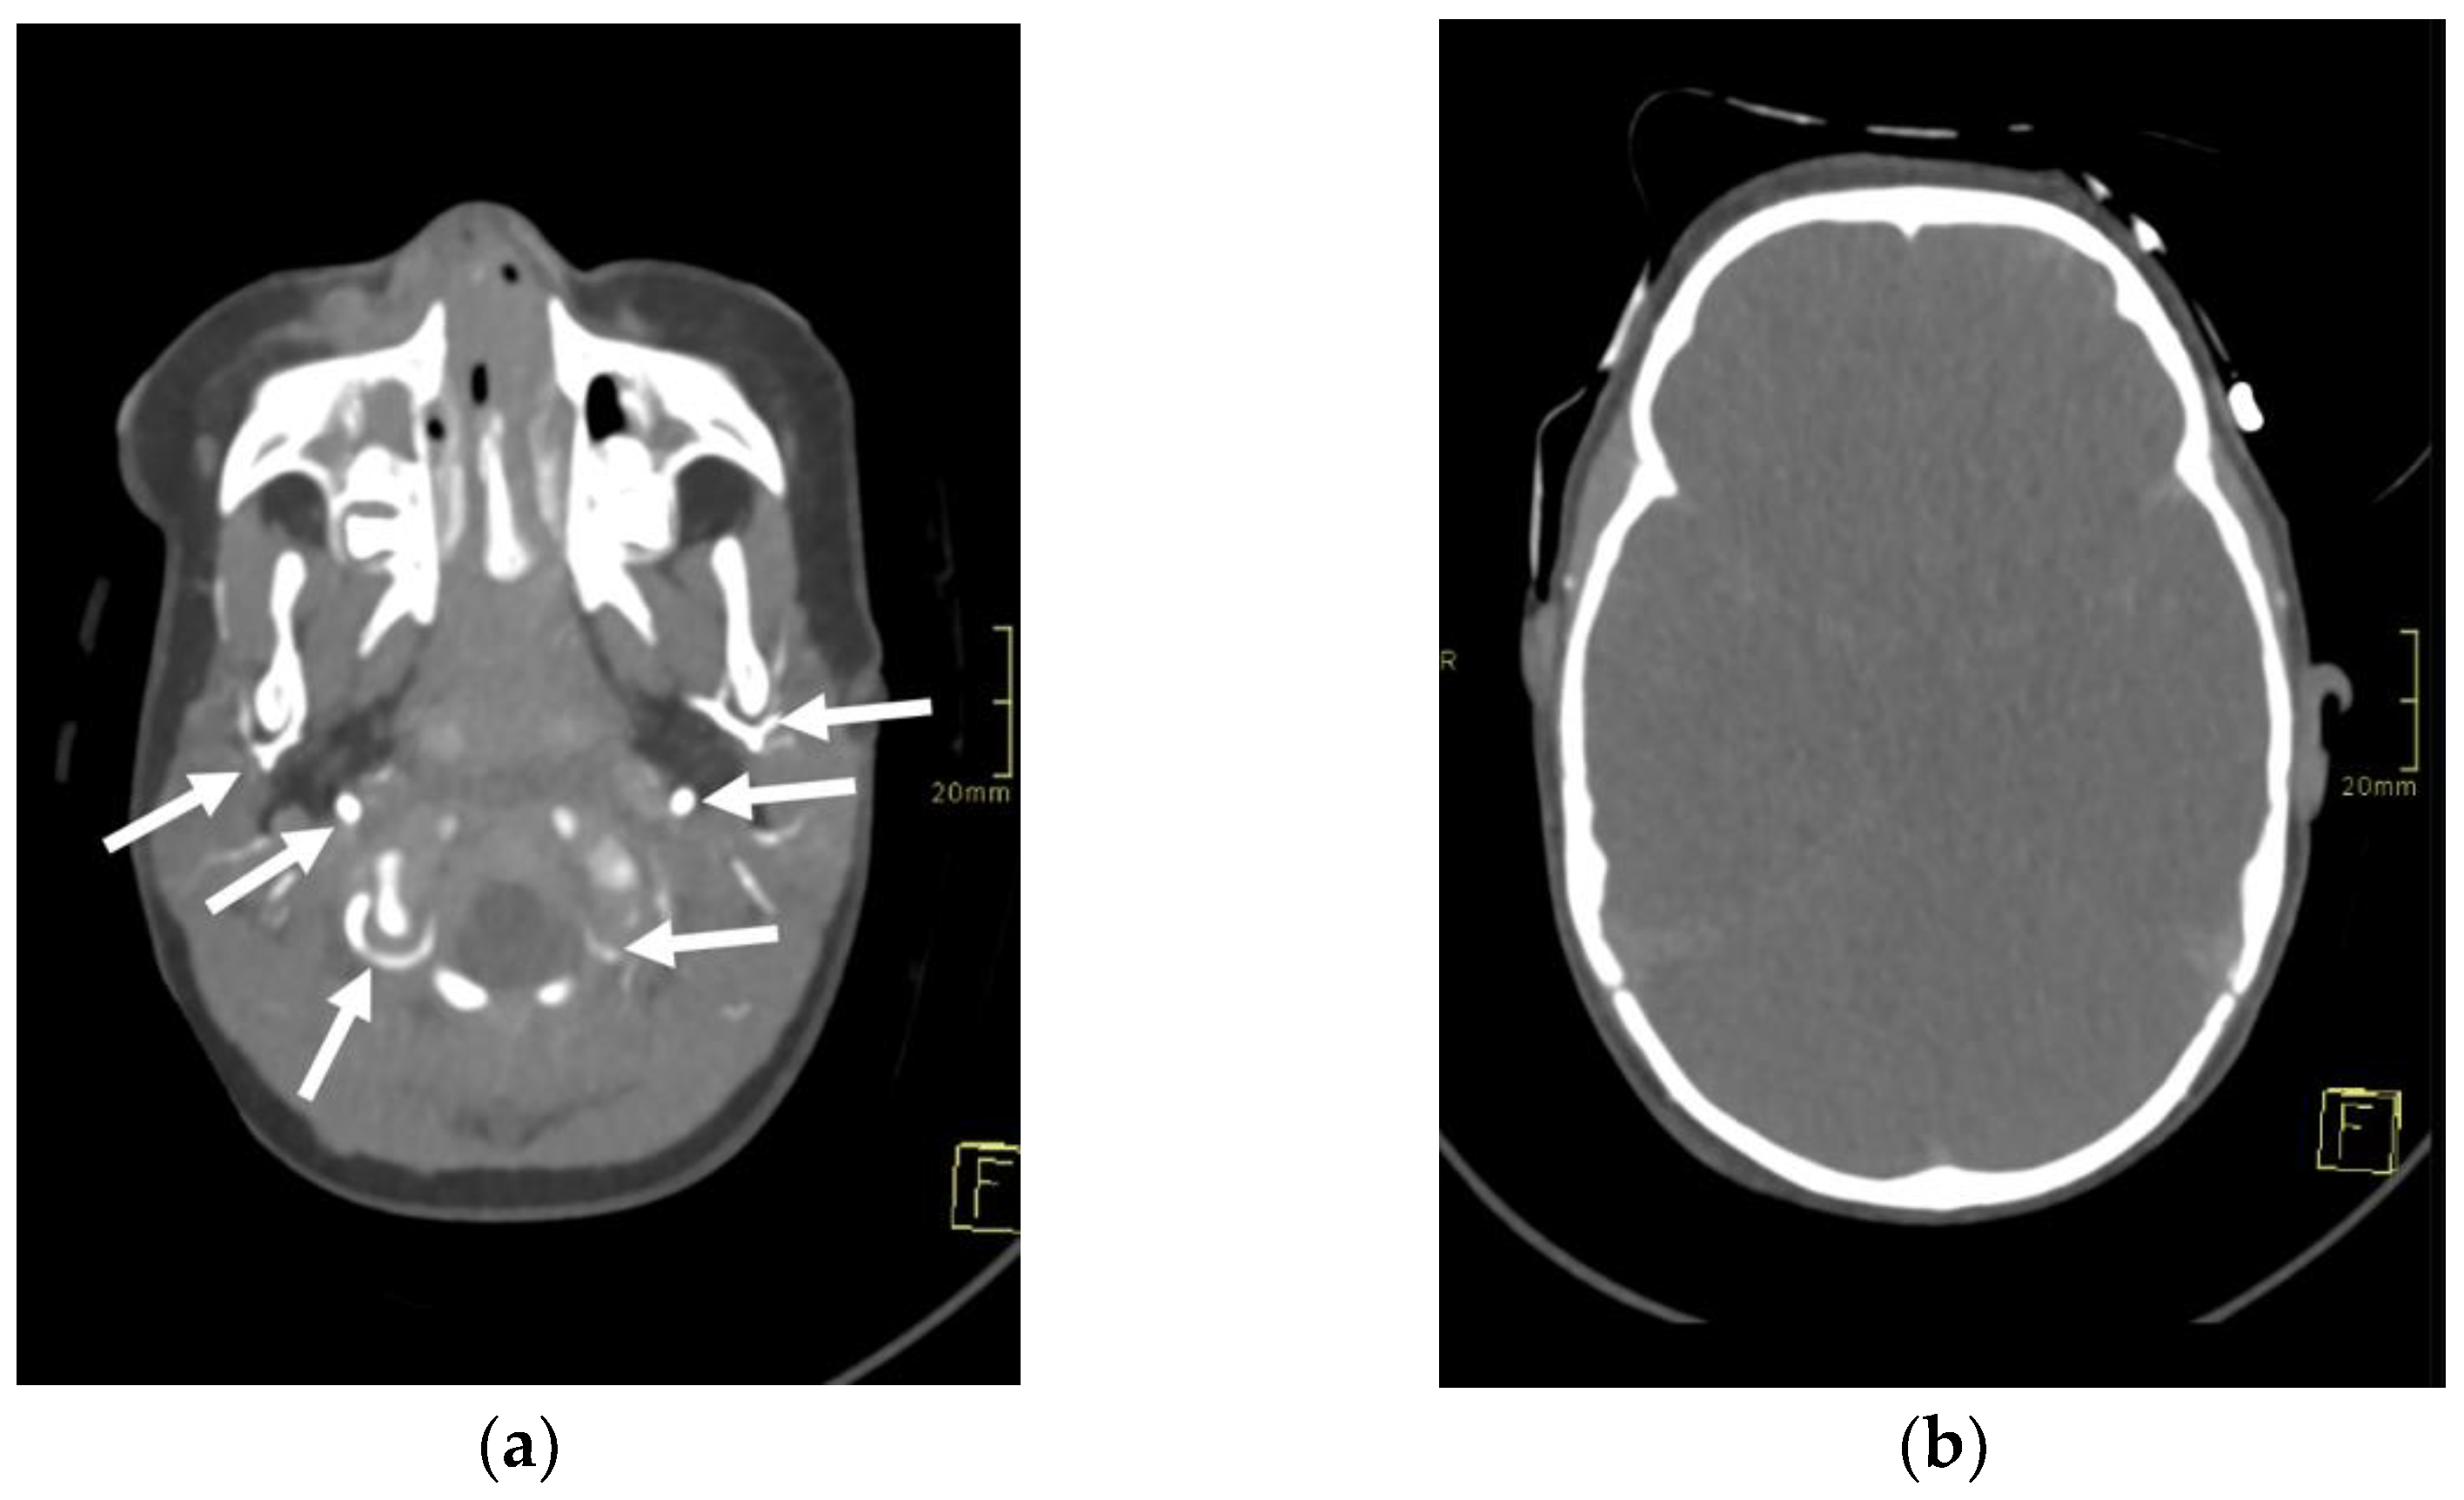

A 1-year-old girl, involved in a traffic collision, was found asystolic with dilatated and nonreactive pupils. The paramedics immediately initiated cardiopulmonary resuscitation, and the patient was transferred to the nearest hospital. At arrival, the girl was still unconscious and asystolic. After 20 min, cardiac action was re-established. On physical examination, numerous wounds and contusions were found on the patient’s head, and bleeds from the nose and ears were observed. Additional contusions were noted on the trunk and extremities. The girl did not react to painful stimuli and had a Glasgow coma scale assessment score of 3. A complete blood count showed low haemoglobin (80 g/L) with elevated serum lactate levels (14 mmol/L). Whole-body computed tomography (CT) was performed forthwith. A head CT disclosed several fractures of the frontal and occipital bones, bilateral subarachnoid haemorrhage in the frontal region, and massive haemorrhage in the right maxillary sinus. No changes were noted in the cervical spine. CT of the chest and abdomen showed multiple contusions of the lungs and haematomas in the mediastinum and right inguinal region. For the treatment of severe hypotension (45/35 mmHg), the patient received blood transfusions, norepinephrine, and dopamine. The patient was transferred to a tertiary hospital centre. As intracranial hypertension (ICP = 40 mmHg) was persisting, treatment with mannitol and analgosedation was initiated. Therapeutic hypothermia was not induced due to the presence of coagulopathy. A follow-up CT scan of the head was performed approximately 12 h after the accident and showed marked cerebral oedema with completely displaced ventricles. The subarachnoid haemorrhage was more extensive, and pronounced transtentorial herniation through the foramen magnum was noted. CT brain angiography disclosed absent blood flow within the cerebral arteries (Figure 1). The patient’s condition continuously deteriorated despite intensive treatment. Due to the poor prognosis, it was decided that further treatment was not feasible, and formal tests to confirm brain death were conducted.

Figure 1. Axial 3-mm-slab maximum intensity projection of the brain computed tomography angiography (CTA) of the 1-year-old infant. The CTA images (a,b) demonstrate absent contrast opacification of the intracranial arteries. Note the normal opacification of the extracranial arteries (arrows).